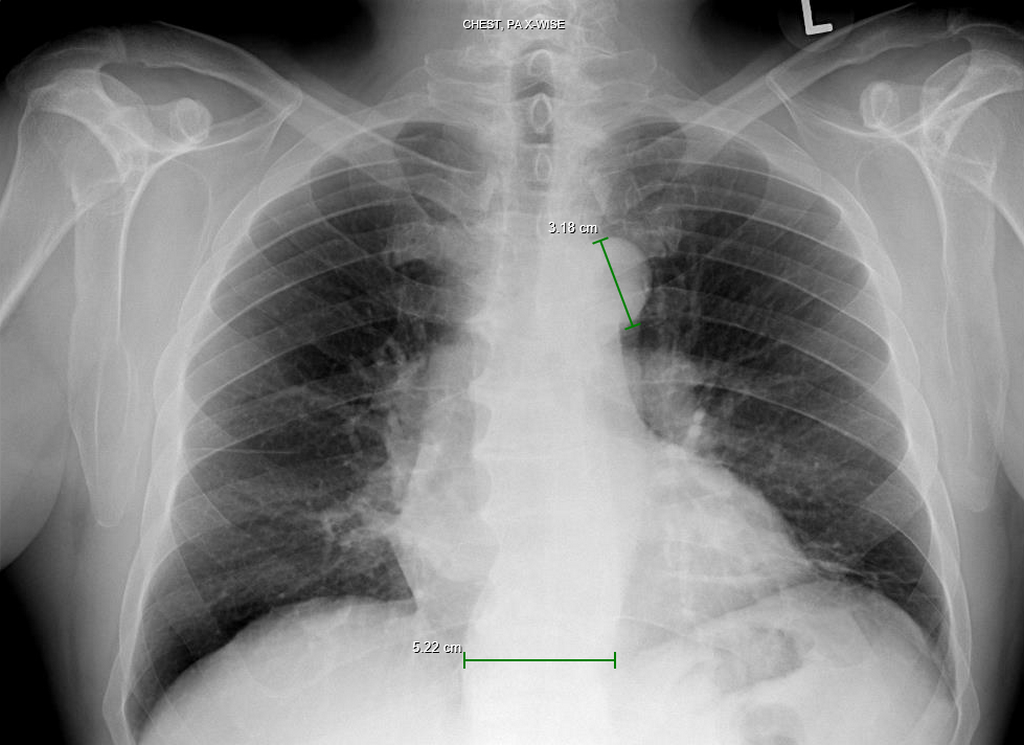

The Measure Distance tool is used to measure the distance between any two points on the image. A sample image with the measurement is shown below.